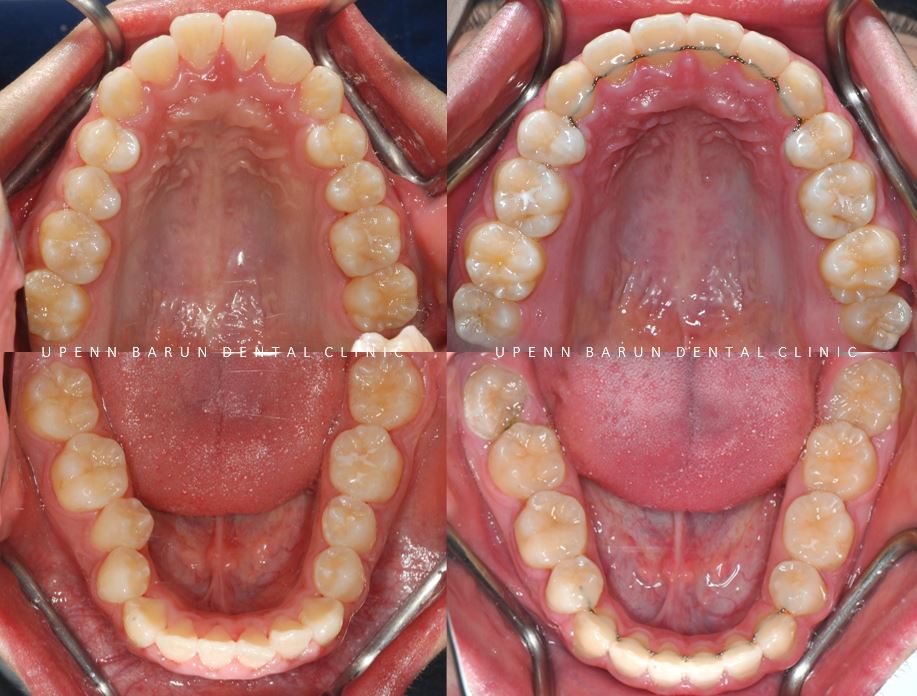

돌출된 앞니를 개선하기 위해서

상대적으로 중요도가 떨어지는

소구치를 발치하고

앞니들이 들어갈 공간을 마련해주어야 하는데요,

그 공간을 이용하여

앞니들을 뒤로 당겨주어야 합니다

교정 전

악궁이 좁아 삐뚤빼뚤했던 치아들이

교정 후

발치된 공간으로 치아들이 올바르게 배열되며

교정치료가 만족스럽게 잘 마무리 되었습니다.

교정완료 후에는

치아들이 원래 위치로 돌아가는 것을 방지하기 위해

상악과 하악의 앞니 뒤쪽에 고정성 유지장치를

붙여 드렸습니다. :)